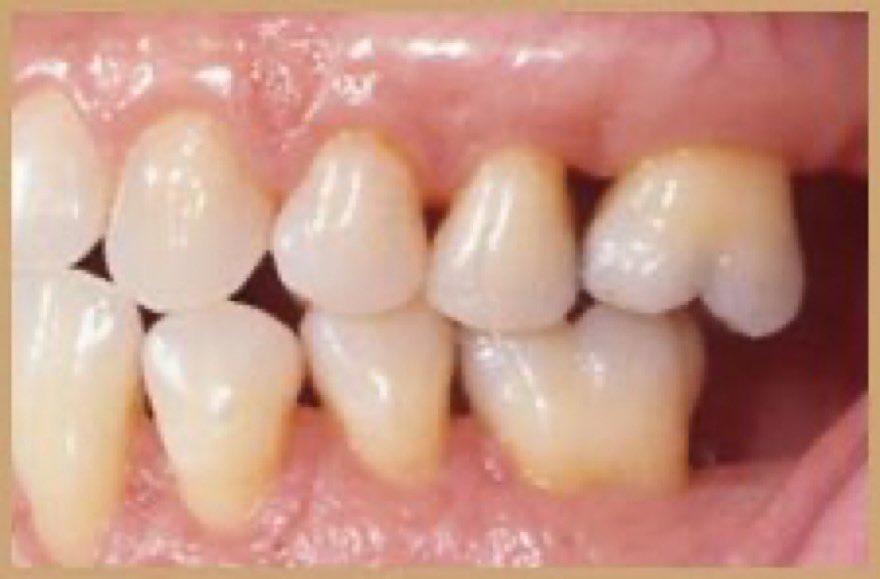

اللثة السليمة:

لمعرفة اللثة المريضة يجب أولا معرفة السليمة ونعرف الاختلافات البسيطة بين جميع الأعراق.اللثة السليمة لونها زهري (غالبا)ملتصقة بالأسنان لامعة(غالبا)لا تنزف عند اللمس أوالتفريش أو بدون سبب/بعض البشرلديهم تصبغات سمراء طبيعية #صحة_أسنانك